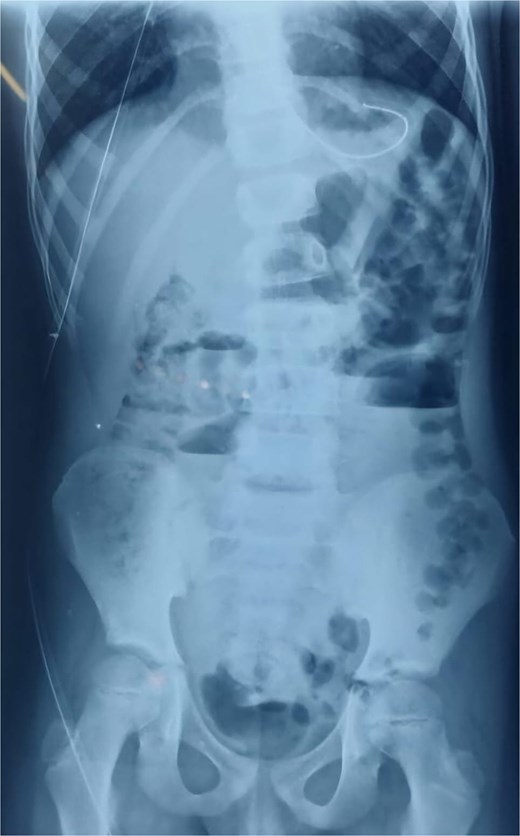

An abdominal X-ray showed multiple dilated bowel loops with air-fluid levels (Figs 1 and 2), consistent with a high-grade intestinal obstruction. Given the patient’s surgical history, a diagnosis of volvulus secondary to intestinal malrotation was strongly considered.

X-ray image at admission showing multiple dilated bowel loops with air-fluid levels.